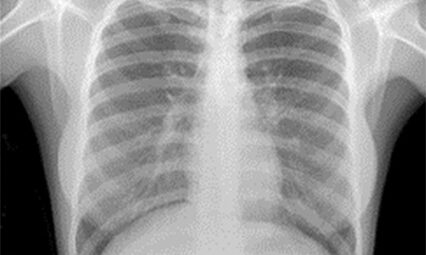

Medical X-rays produce highly detailed images of tissues and structures inside the body. If X-rays traveling through the body also pass through an X-ray detector on the other side of the patient, an image will be formed that represents the shadows formed by the objects inside the body.

Radiological density, a key concept in radiography, is a measure of a material’s resistance to the passage of X-rays. It is determined by both the density and the atomic number (the number of protons in an atom’s nucleus) of the materials being imaged. For example, structures such as bone contain calcium, which has a higher atomic number than most tissues. Because of this property, bones readily absorb X-rays and, thus, produce high contrast on the X-ray detector.

As a result, bony structures stand out distinctly, appearing whiter than other tissues against the black background of a radiograph. This stark contrast is a key feature of radiographs. Conversely, X-rays pass more readily through less radiographically dense tissues, such as fat and muscle, as well as through air-filled cavities, such as the lungs. These structures appear in shades of gray on a radiograph, creating a nuanced visual representation of the body’s internal structures.